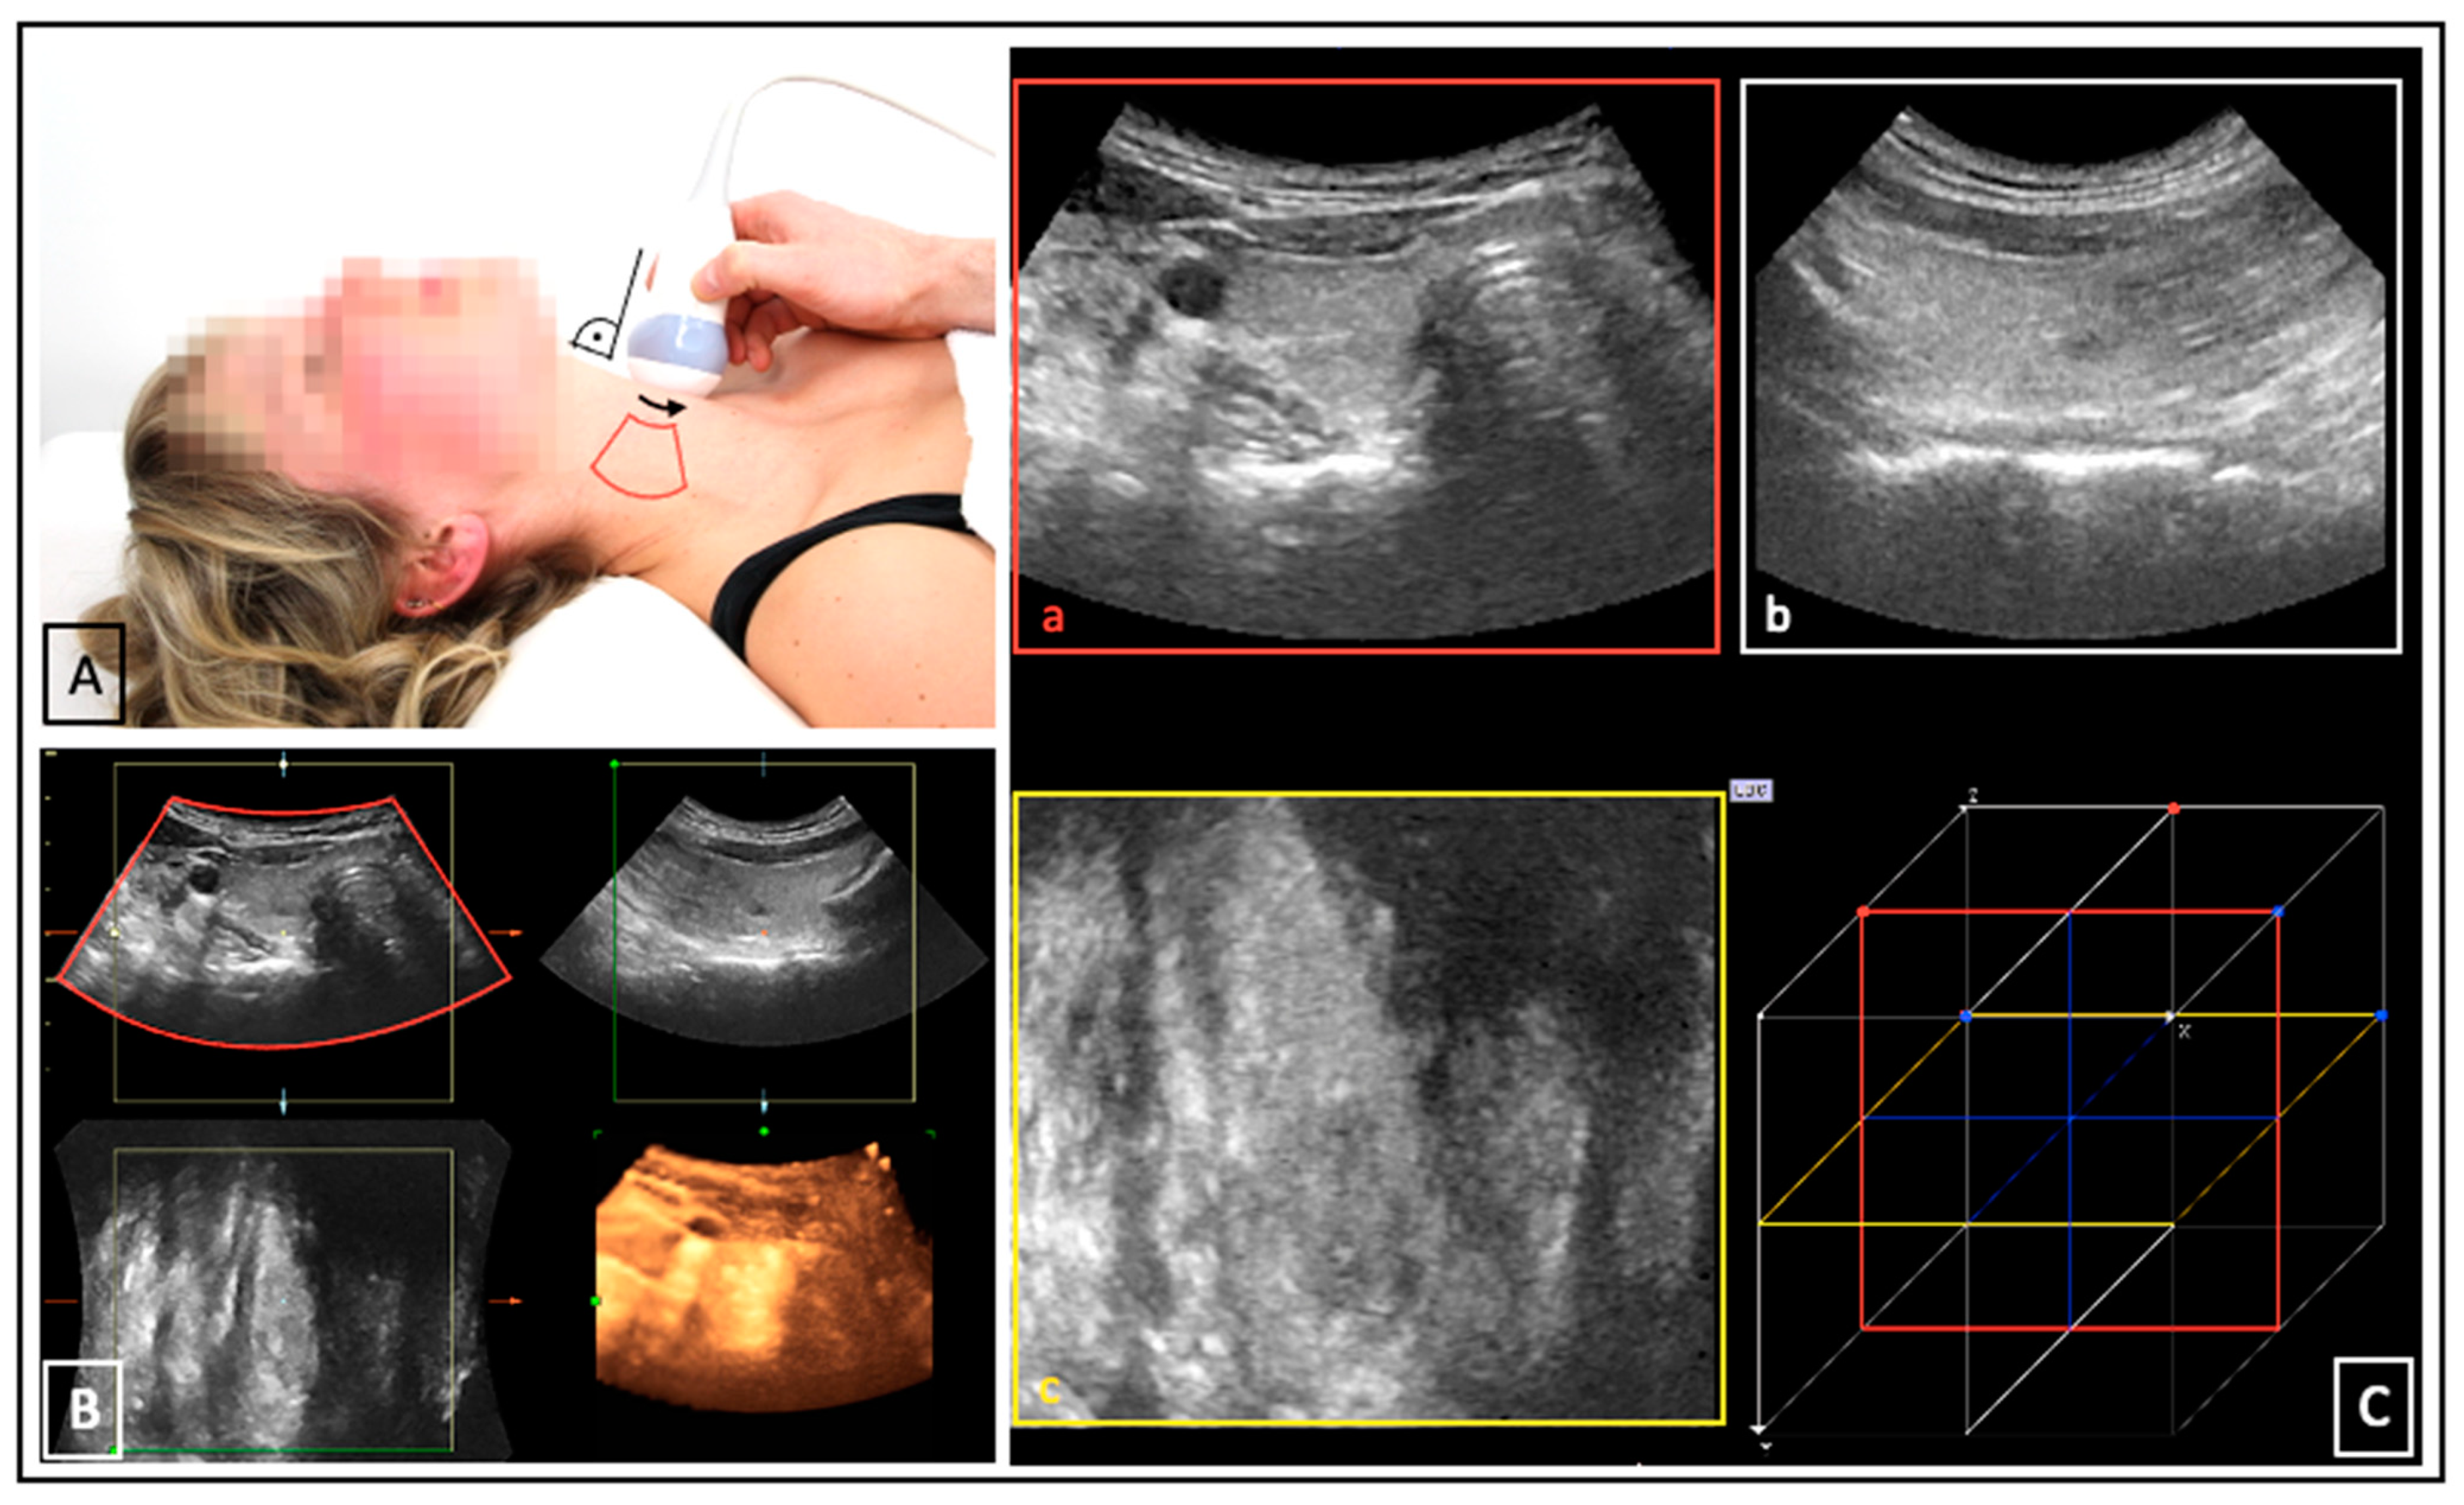

US was performed on the LOGIQ E9 device (GE Medical Systems, Milwaukee, WI, USA). Separate scans of each thyroid lobe (left and right) were acquired. ConUS was conducted with the linear matrix array ML6-15 according to a local standard operating procedure [7]. For 3DsnUS, a magnetic field and specific position sensors equipped to the ML6-15 probe were necessary. For 3DmsUS an automated mechanically swept 3D convex probe (RAB4-8) was used. The methodology of these 3D-US applications has been described in several previous publications [14,19,20]. All 3D-US data sets were transferred to the research software PMOD (Version 4.1, PMOD Technologies Ltd., Zürich, Switzerland). Examination settings and acquired data sets are depictured in Figure 1 and Figure 2.

Figure 1.

3DsnUS: probe movement ((A), black arrow) within the magnetic field generated by a transmitter ((A), red arrow); position sensors ((A), blue arrows) enable reconstruction of 3DsnUS images based on the probe movement and according to the position of the associated 2D frames ((A,B), black, blue, and red boxes). (C) shows a 3DsnUS data set of a right thyroid lobe displayed in the PMOD software in three dimensions: transverse ((C), a, red box), sagittal ((C), b, white box), coronal ((C), c yellow box).

Figure 2.

3DmsUS: constant fixation of the probe orthograde to the neck surface ((A), right angle); movement of the automated mechanically swept acoustic element inside the probe ((A), black arrow), acquired image sector ((A), red box), and reconstructed 3DmsUS data set on the US device (B). (C) shows a 3DsnUS data set of a right thyroid lobe displayed in the PMOD software in three dimensions: transverse ((C), a, red box), sagittal ((C), b, white box), coronal ((C), c yellow box).